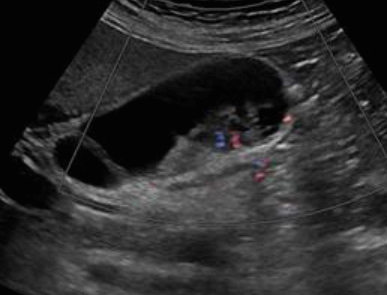

Gall bladder carcinoma (담낭암) adenoma와 adenocarcinoma의 감별

adenoma adenocarcinoma 선종은 변연이 매끈하다 종괴변연이 불규칙하다 wall 이 선명하다 wall 층이 무너져 wall과의 경계가 불분명 mass 안에 color (-) mass 안에 color (+) 선종은 목이있는 유경성이 많다 종괴는 목이없는 무경성이고 wall과 넓게 퍼져있다 GB cancer type